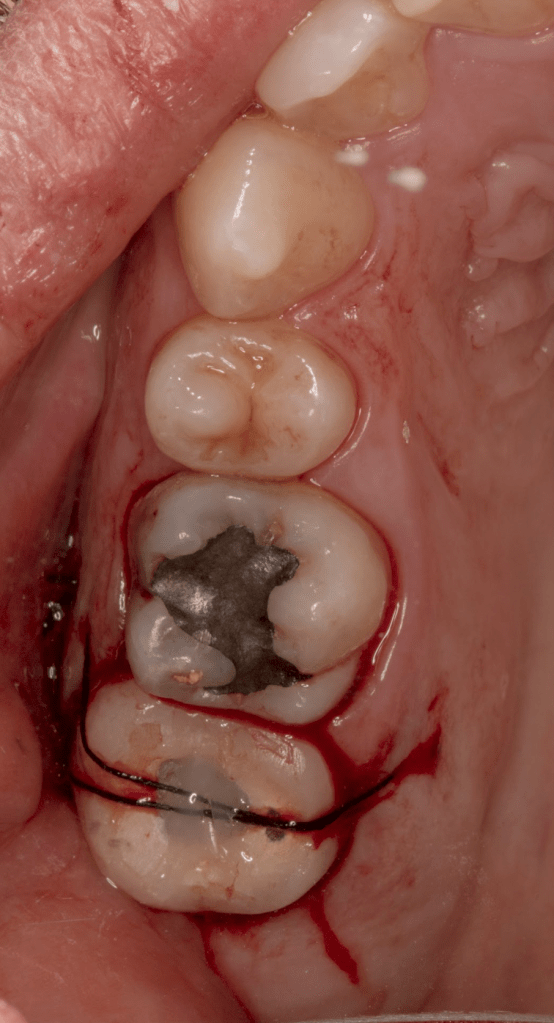

Reco pre-endo gingivectomái, pared yuxtaosea